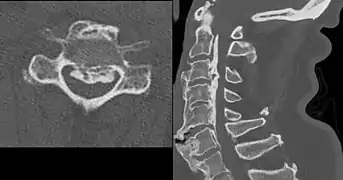

Confluent ossification of multiple contiguous vertebral bodies in diffuse idiopathic skeletal hyperostosis (DISH)

Ossification of the posterior longitudinal ligament in DISH_Nov_2018.jpg.webp)